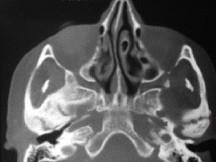

关于颞下颌关节强直(如图)的描述哪项是正确的 ( ) A.颞下颌关节外强直是关节外纤维黏连 B.颞下颌关节内强直是关节内骨性黏连 C.混...

问题 关于颞下颌关节强直(如图)的描述哪项是正确的 ( )

选项 A.颞下颌关节外强直是关节外纤维黏连 B.颞下颌关节内强直是关节内骨性黏连 C.混合性下关节强直是指关节内,外强直同时发生,又称颌间挛缩 D.关节及关节周围组织器质性病变造成开口困难或完全不能开口 E.颞下颌关节强直常常突然发生

答案 D